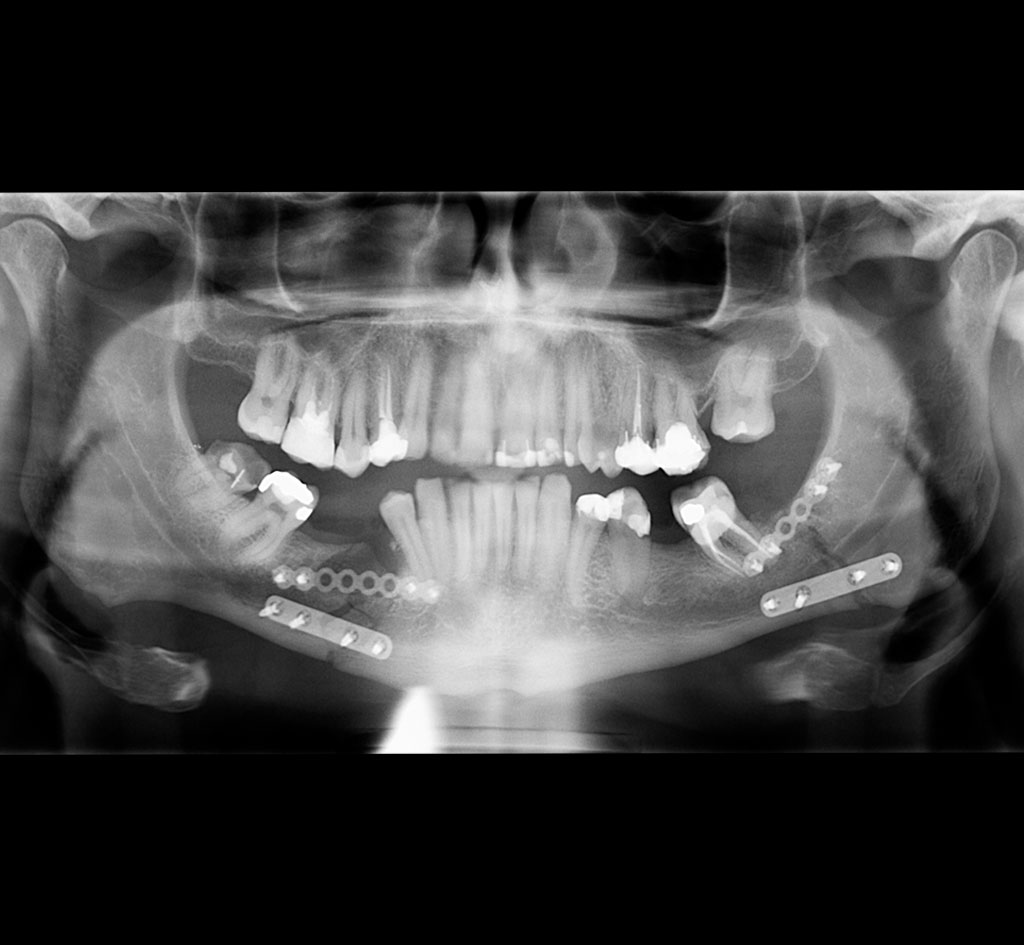

Les spécialistes en chirurgie buccale et maxillo-faciale ont la formation nécessaire pour traiter les patients ayant subi un traumatisme facial. La traumatologie maxillo-faciale comprend tout les types de fractures des os du visage, du front au menton, en incluant les plaies ou lacérations de la peau et des tissus mous, ainsi que les traumatismes dento-alvéolaires.

Les fractures les plus fréquentes sont celles de la mandibule (mâchoire inférieure), celle du tiers moyen du visage (maxillaire supérieur, os malaire, plancher de l’orbite).

La consultation initiale est généralement faite en milieu hospitalier. La chirurgie pour traiter les fractures est faite sous anesthésie générale. Une hospitalisation de courte durée est nécessaire dans la majorité des cas. Les cas plus complexes pourraient nécessiter une période d’hospitalisation plus longue.